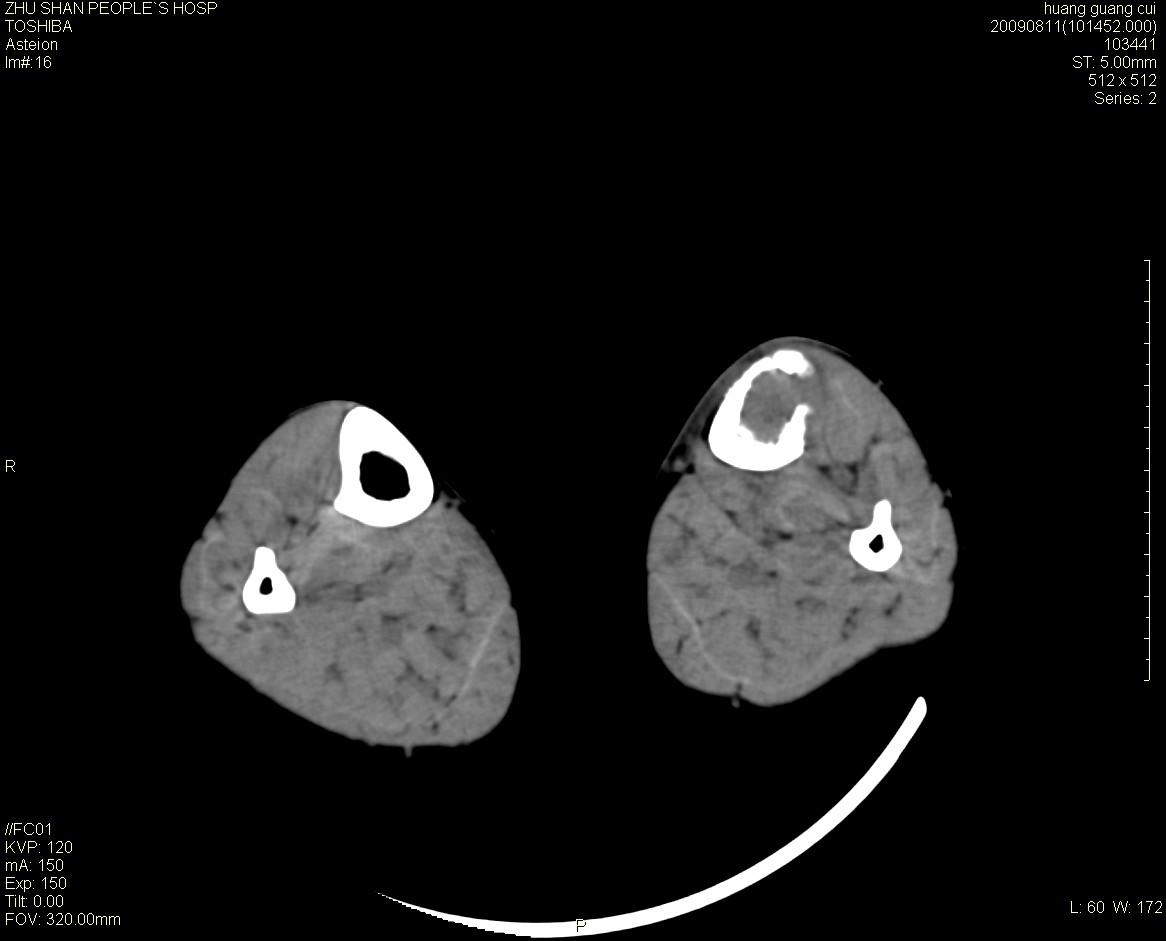

标题: CT21557:女性 56岁 左胫骨中断肿痛2月余。 [打印本页]

标题: CT21557:女性 56岁 左胫骨中断肿痛2月余。

女性 56岁 左胫骨中断肿痛2月余。转移瘤or尤文氏肉瘤?

左侧胫骨中段骨皮质溶骨性破坏,髓腔内外见软组织肿块,无明显钙化及成骨,定位相显示病变周围“筛孔样”改变,定性恶性无疑,原发或转移均有可能,倾向于骨纤维肉瘤可能性大,转移瘤不排除。膝关节以下骨转移很少,且要有原发灶支持,尤文氏肉瘤年龄太大不支持。